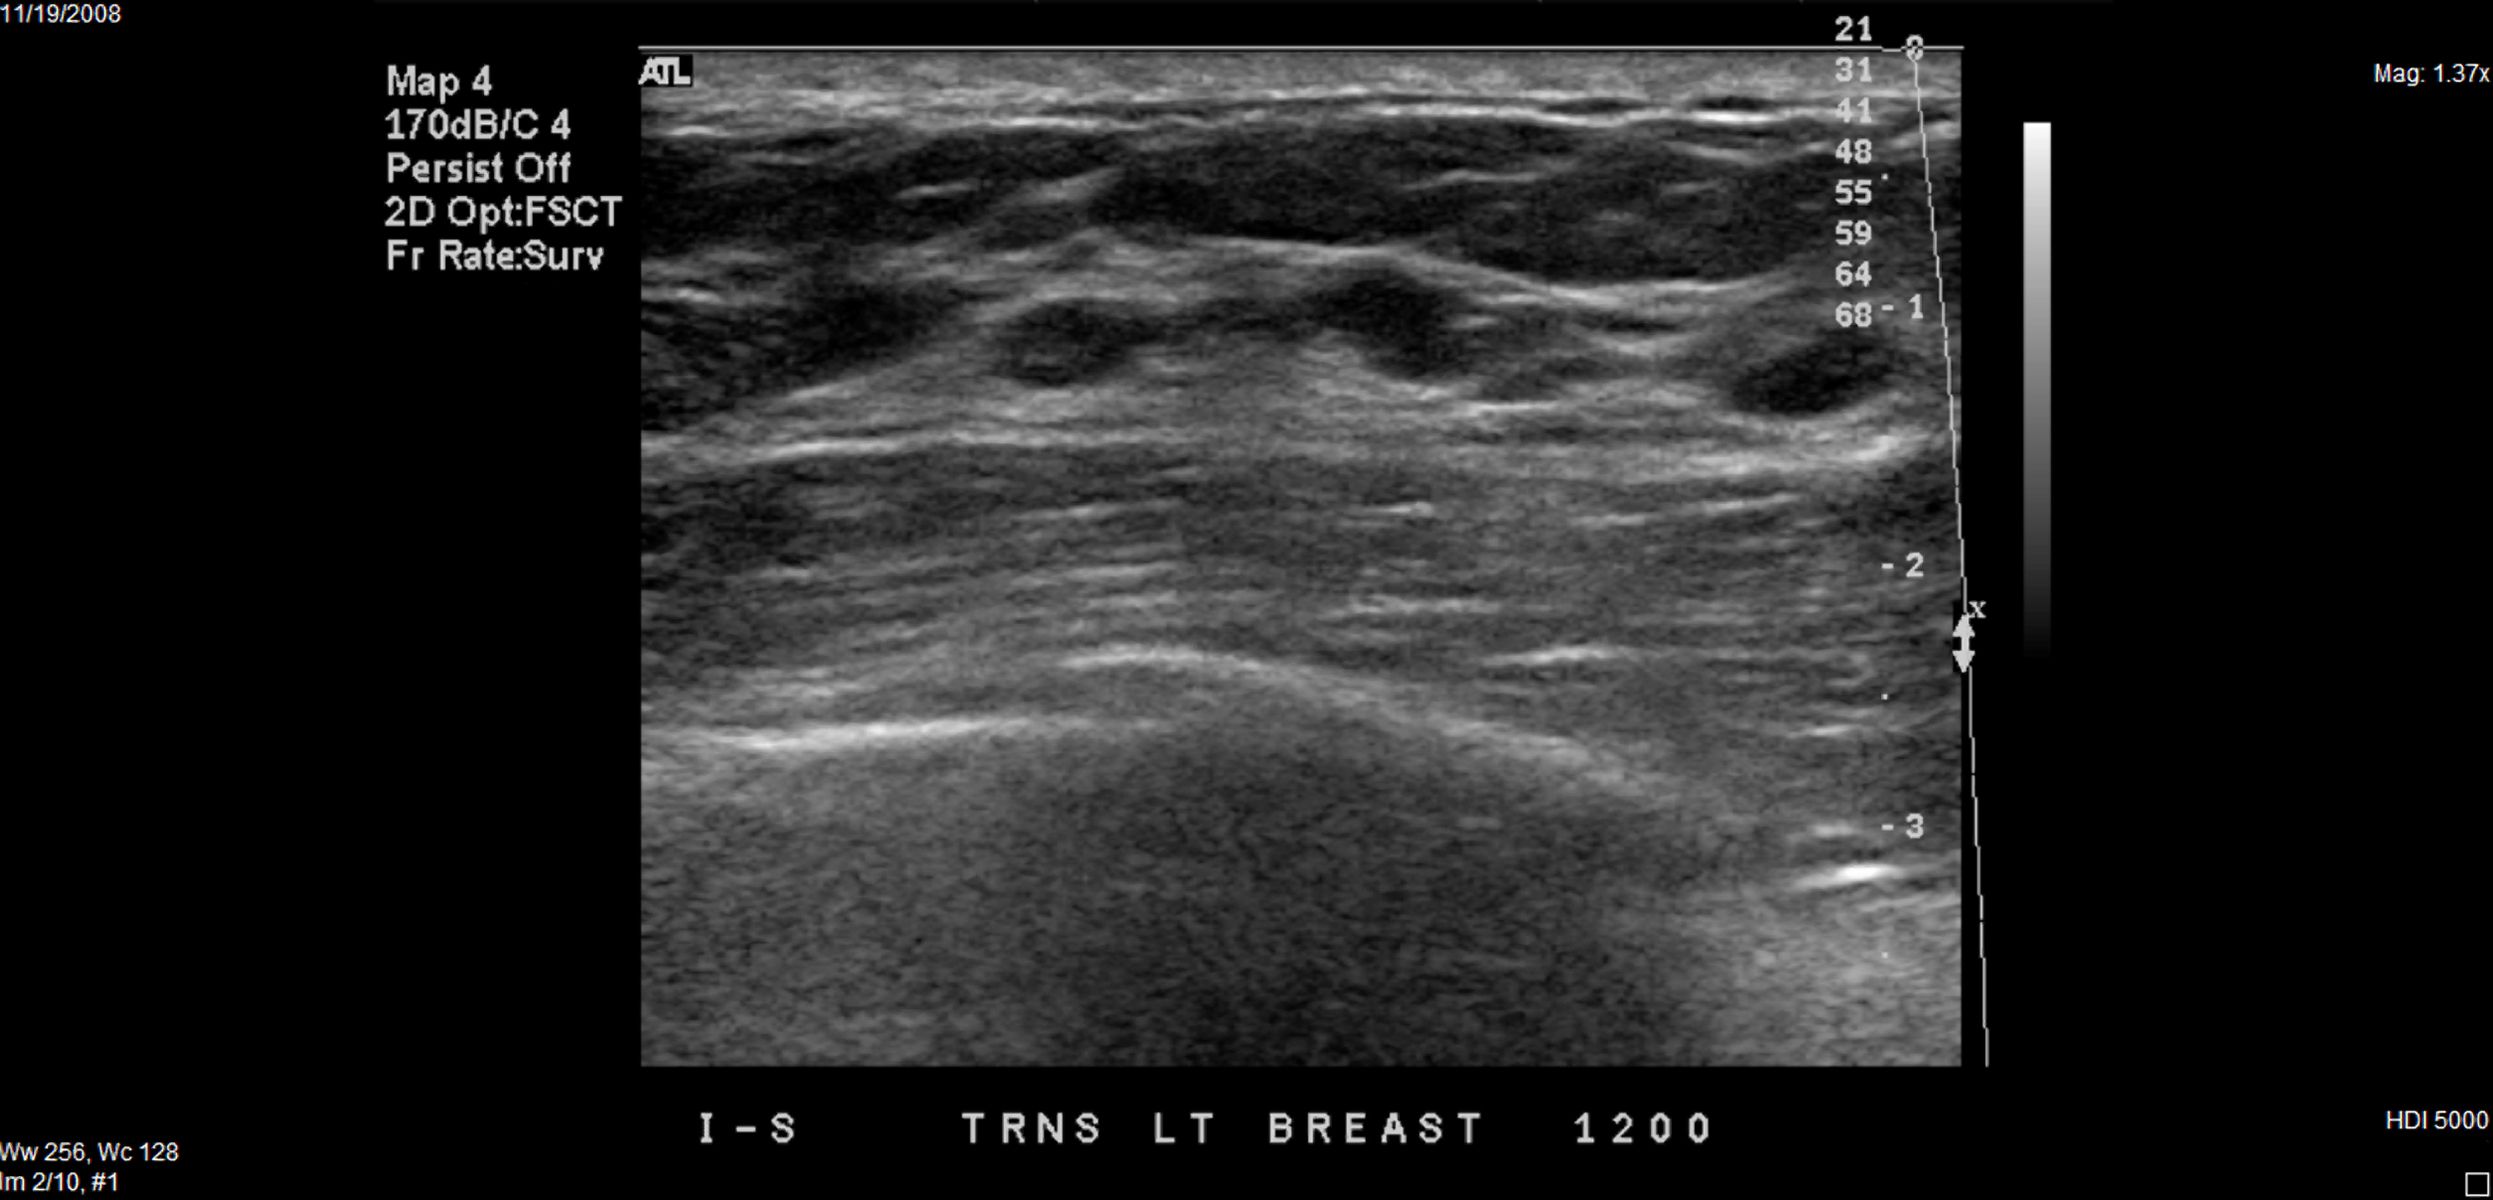

L'ecografia del seno utilizza onde sonore ad alta frequenza per produrre immagini dettagliate dei tessuti del seno. Questo esame è spesso utilizzato come complemento alla mammografia, specialmente in donne con tessuto mammario denso.

L'ecografia è particolarmente utile per distinguere tra cisti piene di liquido e masse solide, fornendo una visione chiara della natura della massa.